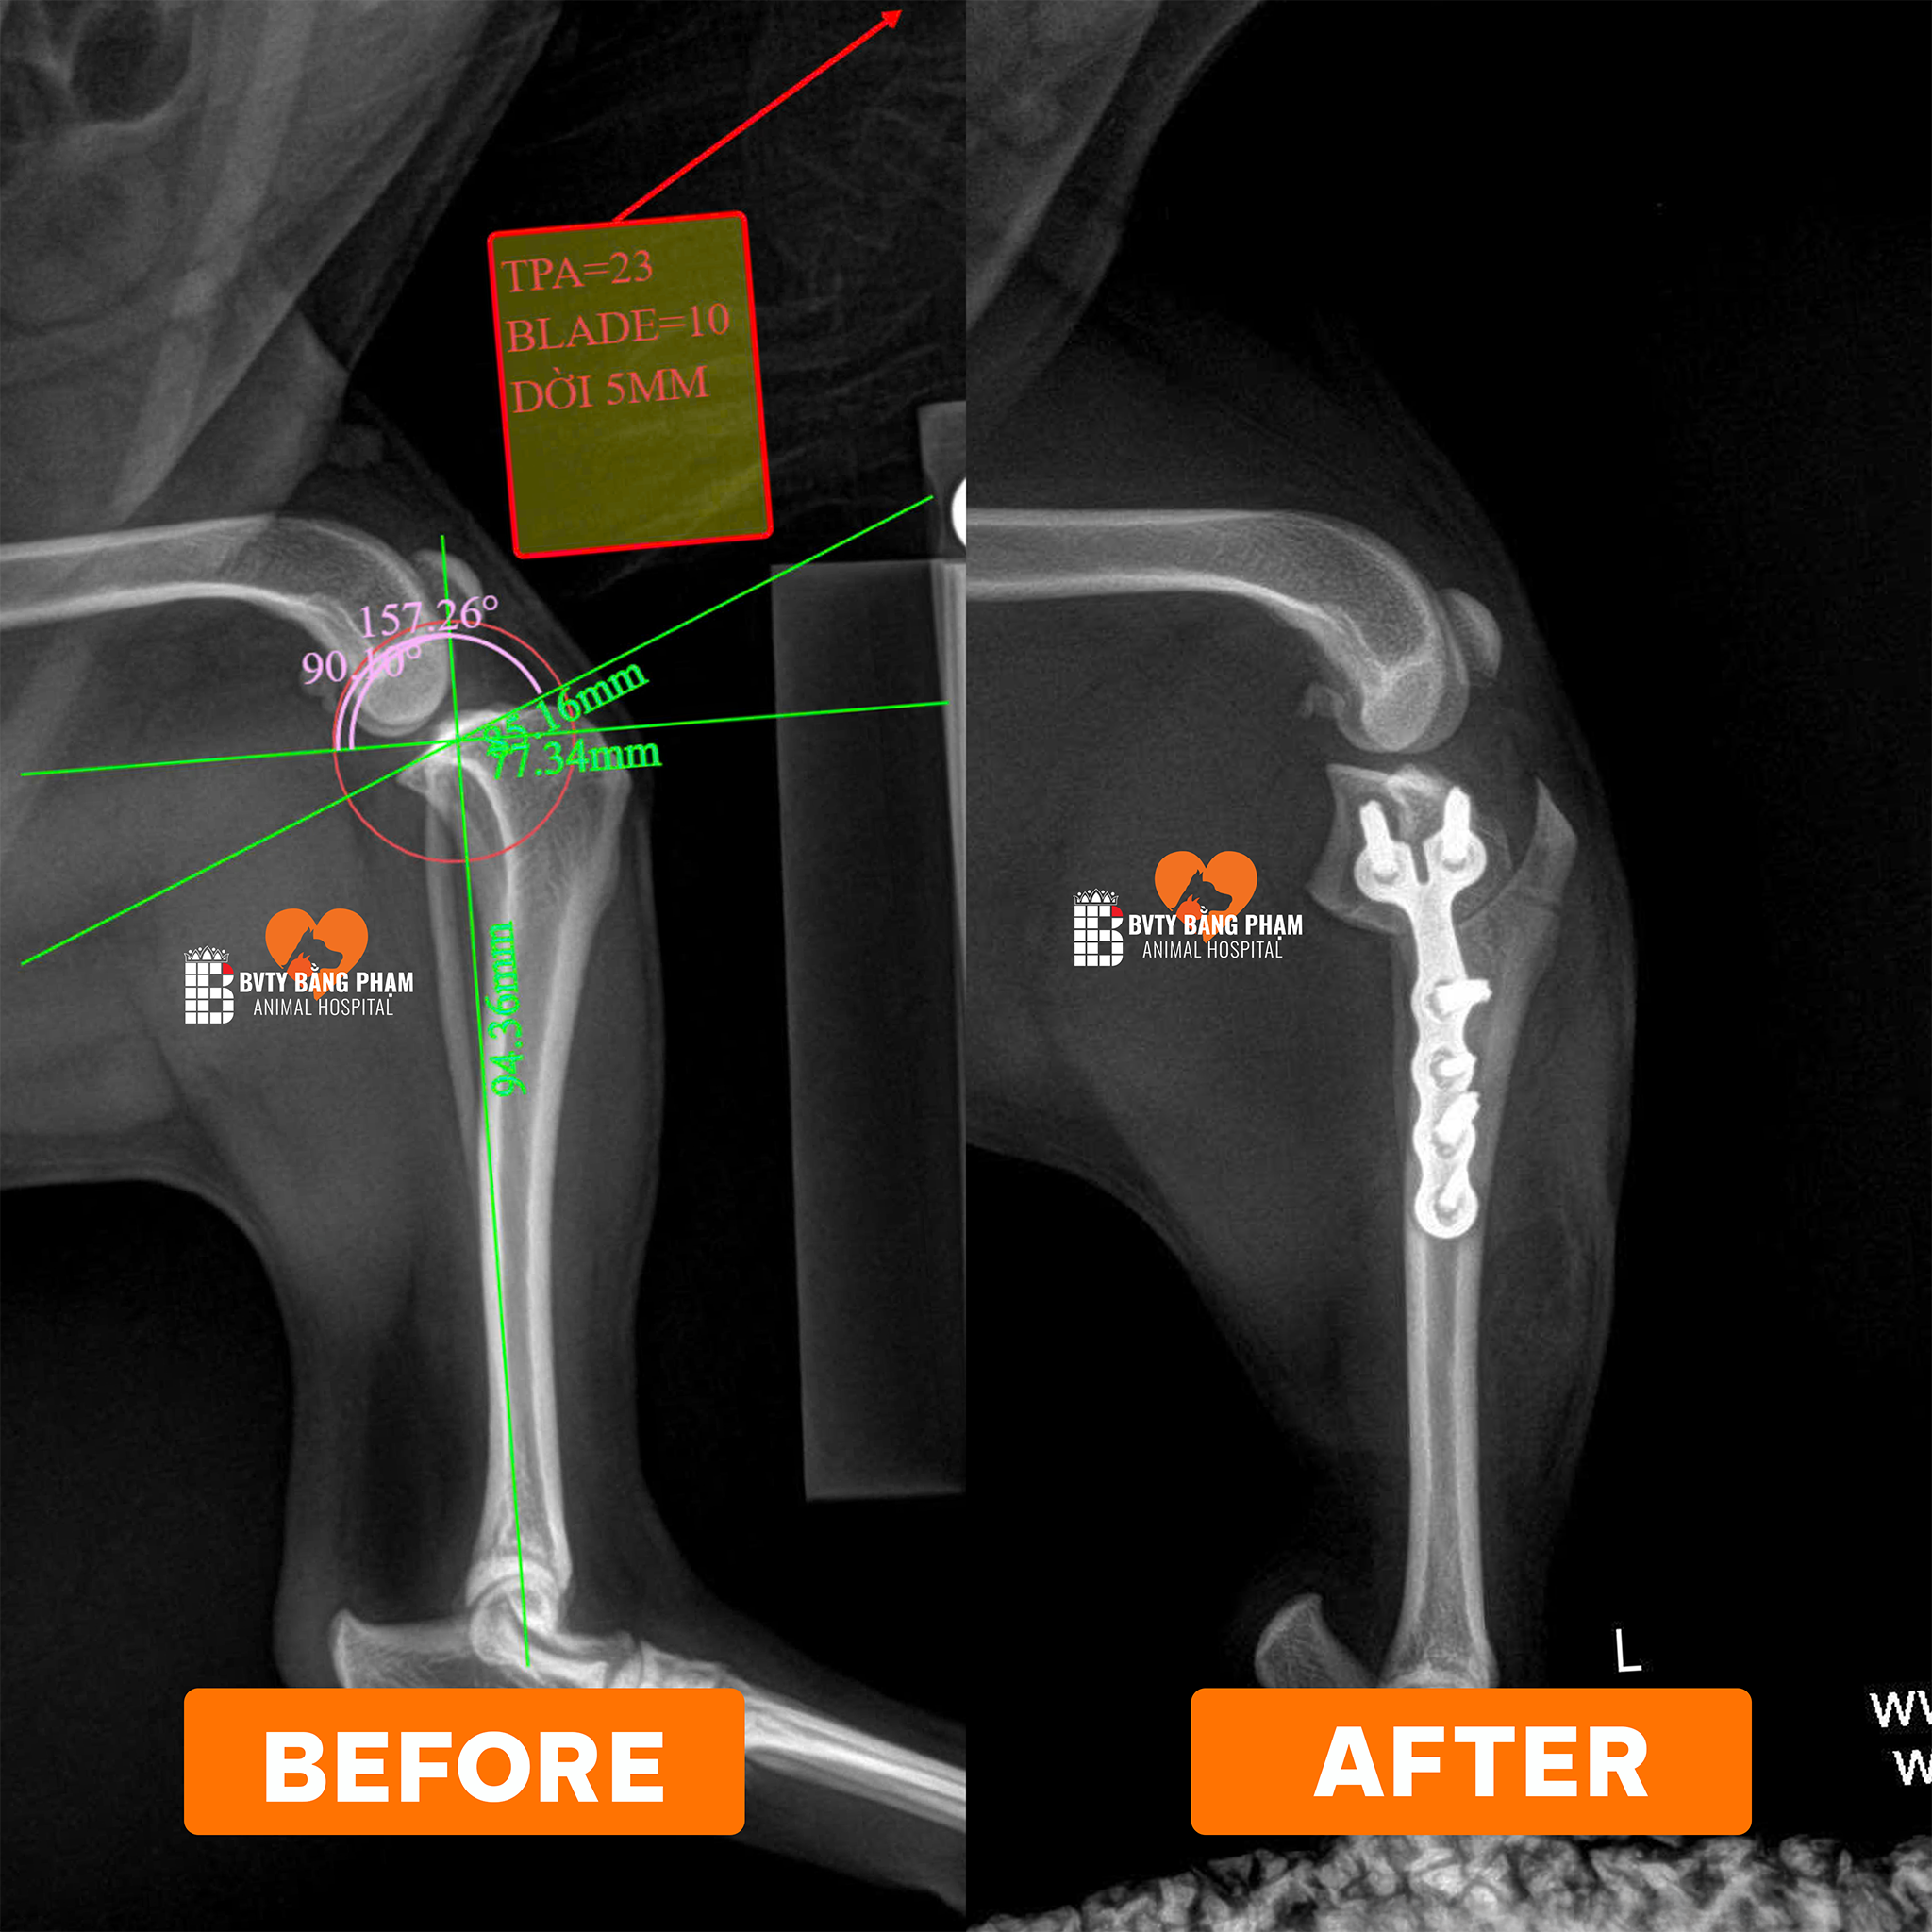

- X-quang: Phát hiện hẹp khoảng cách đốt sống C3 – C4.

X-quang cổ cho thấy khoảng cách giữa đốt sống C3 – C4 bị thu hẹp, gợi ý đĩa đệm cổ thoát vị.

X-quang cổ cho thấy khoảng cách giữa đốt sống cổ C3 và C4 bị thu hẹp, gợi ý đĩa đệm cổ bị thoát vị. Hình ảnh X-quang bên cho thấy đĩa đệm bị đẩy từ phía bụng ra sau, đây là thông tin quan trọng cho quá trình phẫu thuật loại bỏ đĩa đệm.